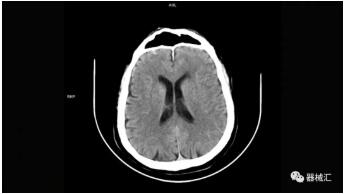

▲ SOMATOM On.site圖像